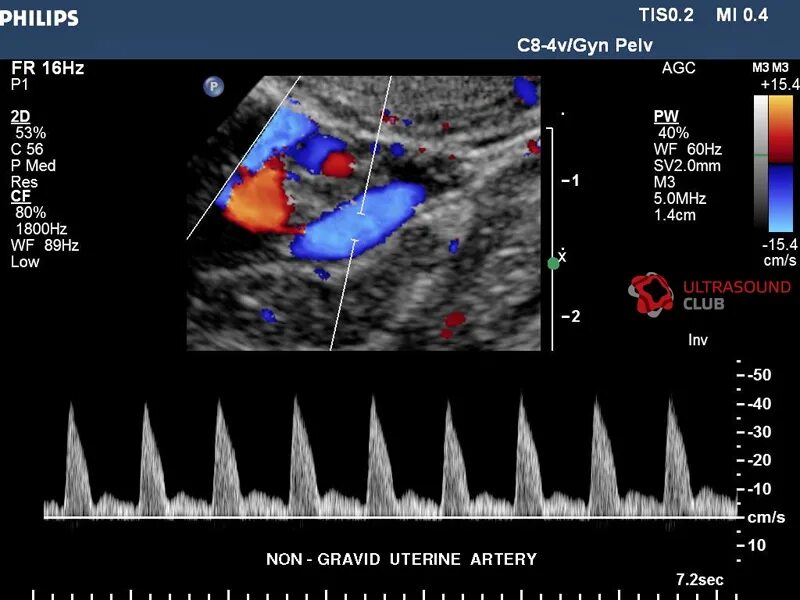

Допплерометрия маточных